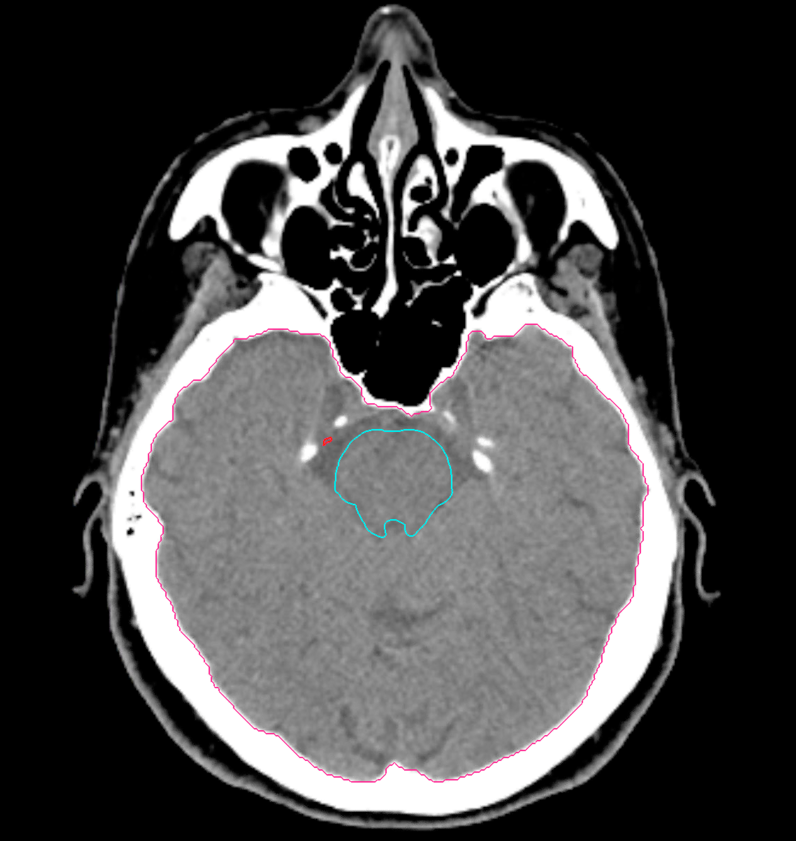

Planning CT Images